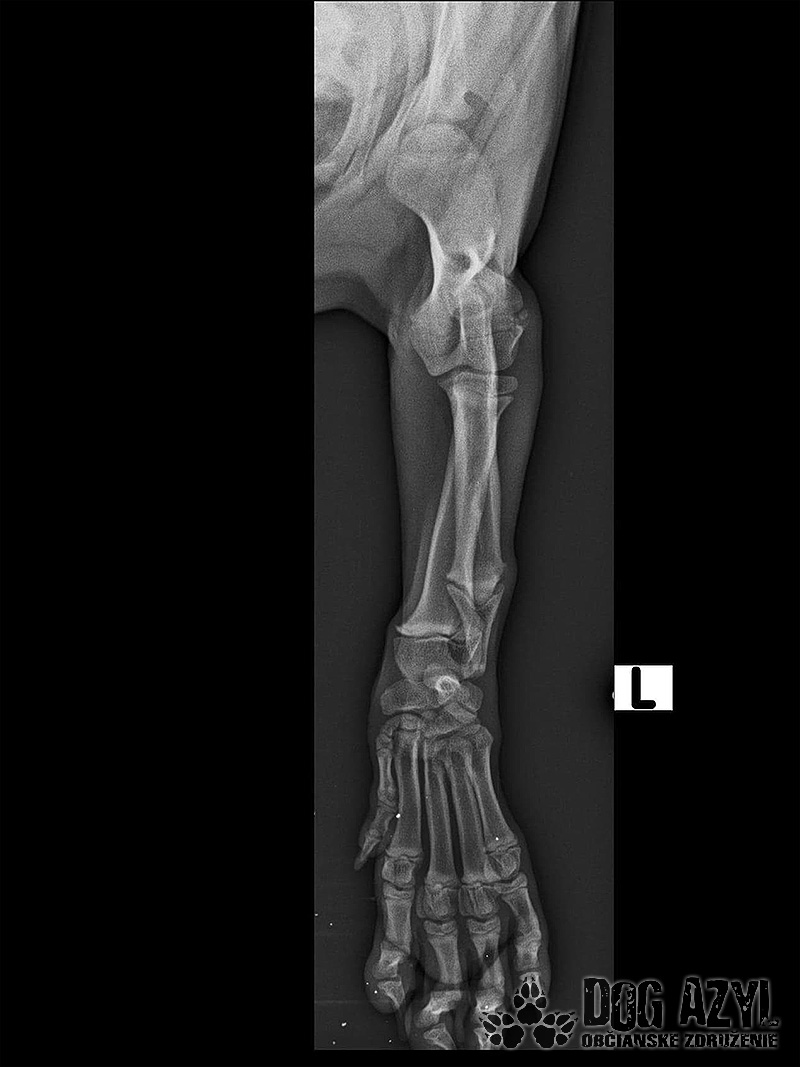

Odoberal sa od drogovo závislých asociálov, ktorý boli vysťahovaný z domu. Ihly, striekačky, ľudské výkaly, rôzne neidentifikovateľné zvratky, špinavé oblečenie, použité kondómy - to všetko nahádzané na jednu kopu v obývačke, kde Pluto so svojou maminkou Miou žili. :( Nevieme ako sa to stalo, kto mu ublížil, ale Pluto má prestrelenú prednú nohu! Viete si predstaviť toho psychicky narušeného človeka, ktorý strieľa na malé bezbranné šteniatko? V dôsledku strelnej rany má doslova rozdrvenú lakťovú kosť. Mali sme veľké obavy, že o nožičku príde, ale MVDr. Vatolík s teamom veterinárnej kliniky Sibra centrum opäť urobil zázrak a malému nožičku napravil a prognóza je viac než dobrá. Čaká ho ešte dlhá cesta k zotaveniu, ale je to odvážny a statočný bojovník. Nechceme si ani len predstaviť čím všetkým si tie zvieratká muesli prejsť, a kto vie koľko ich pôvodne bolo.. Nikto nevie ako a kde skončili Plutovi súrodenci...